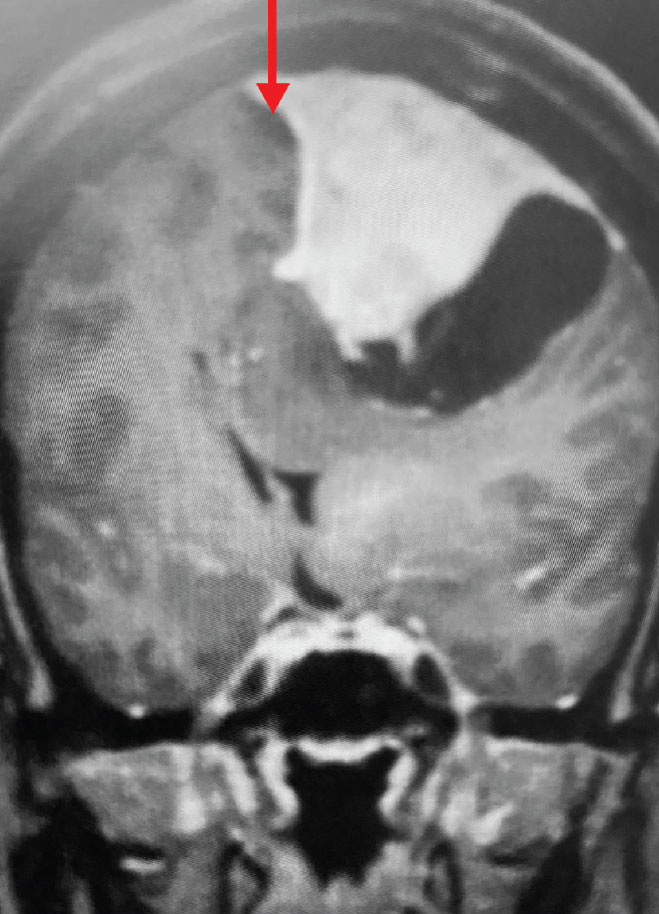

Fig 1. A) Pre-operative, post-contrast, coronal MRI. Arrow points to tumor involvement in the superior sagittal sinus.

Meningiomas that involve the superior sagittal sinus: Sometimes convexity or falx meningiomas will grow into the superior sagittal sinus. Sometimes the sinus can become completely occluded. Usually this occurs over many years, and as such, the brain has time to develop venous collaterals. So, while in a normal person, sudden occlusion of the superior sagittal sinus could lead to venous infarction or death, the very gradual occlusion that can be seen with meningiomas, does not lead to these problems. Also, if the sinus is filled with tumor and completely occluded, it can usually be safely removed at that segment.

This is a 55 year old right-handed woman who was having progressive balance problems. MRI with and without contrast demonstrated a 7 cm partly cystic meningioma involving the left frontal convexity and falx, and encasing the superior sagittal sinus. There was also tumor involvement of part of the convexity skull.